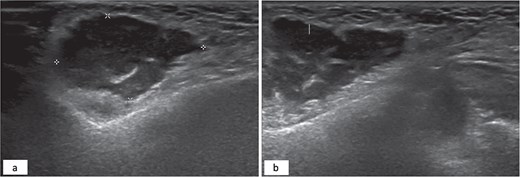

A 34-year-old female patient presented to oral and maxillofacial surgery at the Dental Specialist Center, Hafar Al-Batin, Saudi Arabia, with a complaint of painless right-sided facial swelling for 1 year. The patient reported the injection of a cosmetic filler material 10 years ago. The swelling was a localized nodular and measured approximately 2 × 2 cm, and it was not tender. The patient did not report any pus discharge, and the swelling grew slowly. No gross cranial nerve defects were observed while dental status was good, and no odontogenic etiology was detected. Ultrasound was performed and revealed a subcutaneous collection with internal septa and an irregular wall adjacent to the echogenic fat (Fig. 1).

Hypoechoic subcutaneous lesion with an irregular border measuring 3 × 2 cm with internal echoes adjacent to the echogenic fat (a). Internal septation of the hypoechoic lesion (b).